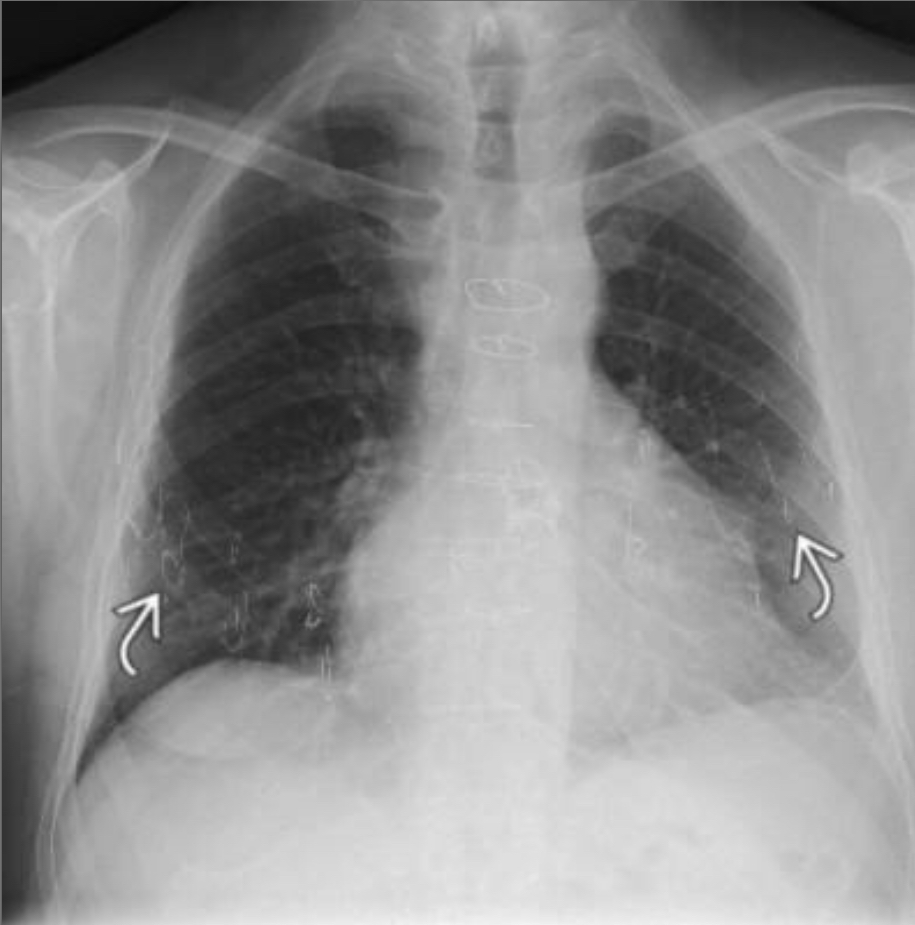

Lymphangioleiomyomatosis (LAM)

Large thin-walled cysts diffusely distributed in the lungs that will eventually replace the entire lung parenchyma.

exclusive to women of child-bearing age, except for TS associated in men

–lymphangiomas and AMLs are commonly associated.

–A/w chylothorax

49 year old woman with a rash on her face. CT chest with multiple thin walled cysts

LAM

a/w renal AMLs and LAD, seen here

Almost exclusively middle aged women although can also occur in TS

p/w exertional dyspnea, recurrent PTX is common